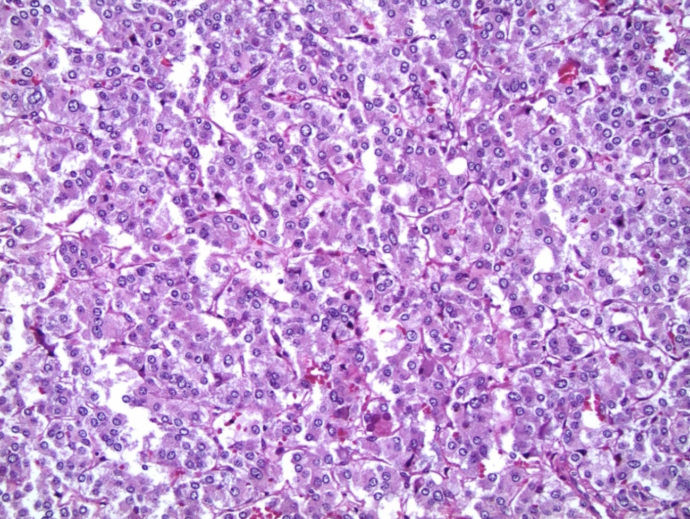

Pheochromocytoma